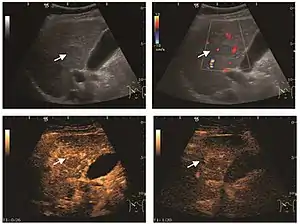

It is a tumor developed secondary to a circulatory abnormality with abundant arterial vessels having a characteristic location in the center of the tumor, within a fibrotic scar. A radial vessels network develops from this level with peripheral orientation. The tumor's circulatory bed is rich in microcirculatory and portal venous elements. The incidence is higher in younger women and tumor development is accelerated by oral contraceptives intake. 2D ultrasound appearance is a fairly well-defined mass, with variable sizes, usually single, solid consistency with inhomogeneous structure. Rarely the central scar can be distinguished. Spectral Doppler examination detects central arterial vessels and CFM exploration reveals their radial position. CEUS examination shows central tumor filling of the circulatory bed during arterial phase and completely enhancement during portal venous phase. During this phase the center of the lesion becomes hypoechoic, enhancing the tumor scar. During the late phase the tumor remains isoechoic to the liver, which strengthens the diagnosis of benign lesion.